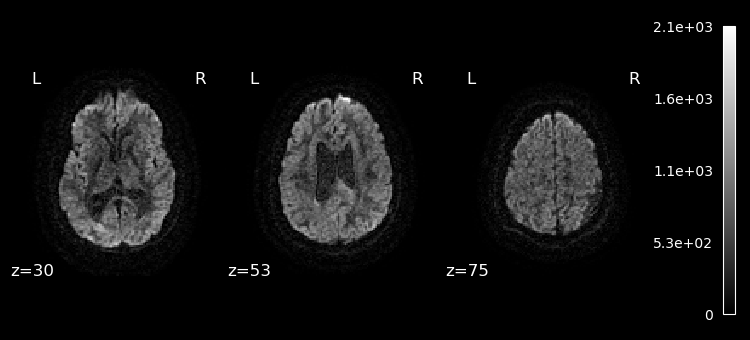

Lets plot the first 10 volumes.

%matplotlib inline

from nilearn import image

from nilearn.plotting import plot_epi

selected_volumes = image.index_img(dwi, slice(0, 10))

for img in image.iter_img(selected_volumes):

plot_epi(img, display_mode="z", cut_coords=(30, 53, 75), cmap="gray")